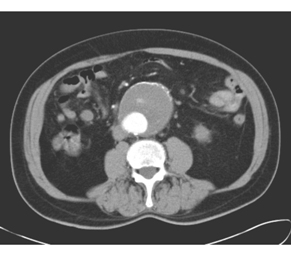

患者,男,65歲。行腹部CT增強掃描,發現腹主動脈異常,如下圖:

3.本例應診斷為

A.主動脈夾層動脈瘤

B.主動脈硬化

C.主動脈血栓形成

D.主動脈瘤

E.主動脈破裂

4.對該病術前評價和術后隨訪的最佳方法是

A.X線平片

B.DSA

C.MSCTA

D.超聲

E.MRI

正確答案:3.D;4.C